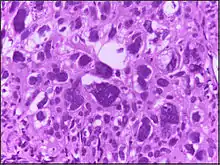

The phrase giant cell is also frequently used, especially with carcinoma.

Giant cell tumors include giant-cell tumor of bone, giant-cell tumor of the tendon sheath,[1] and giant cell fibroblastoma.[2]